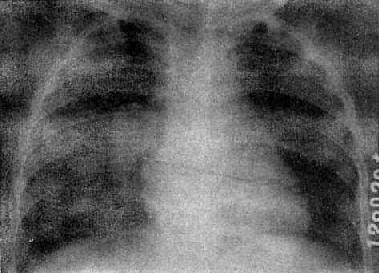

由于病灶系多次血行播散所形成,故X线表现为大小不一、密度不同、分布不均的多种性质的症灶(图3-1-23)。小者如粟粒,大者可为较大的结节状,主要分布于两肺上、中野,下野较少。早期播散的症灶可能已经钙化,而近期播散的病灶仍为增殖性或渗出性。本型结核发展较慢,经治疗新鲜病灶可以吸收,陈旧病灶多以纤维钙化而愈合。恶化时病灶可融合并形成空洞或逐渐转为慢性纤维空洞型肺结核。

图3-1-23 慢性血行播散型肺结核

两肺野布满大小不一、密度不同、分布不均的病灶,

下野较少,膈位置低而平